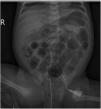

At 14 days post birth, the patient developed anaemia (haemoglobin, 7.7g/dL; normal range, 12.5–20.5), leading to administration of IVIG (1g/kg IV over 6h). The patient remained haemodynamically stable before and during treatment. The anaemia progressed despite IVIG (haemoglobin, 6.7g/dL 12h after immunoglobulin administration), so the patient underwent partial exchange transfusion (80cc/kg) delivered through a central venous catheter (left femoral vein). There were no adverse events associated with the transfusion. The haemoglobin concentration increased to 12.3g/dL (Fig. 1). A few hours after the transfusion was completed, the patient exhibited general deterioration with abdominal distension and bilious vomiting. She required endotracheal intubation and haemodynamic support with dopamine. The findings of the abdominal radiograph were suggestive of NEC (Fig. 2). The patient underwent an urgent laparotomy that confirmed the diagnosis. This was followed by performance of an end ileostomy with removal of the distal ileum and ascending colon. After the surgery, the patient recovered gradually and was discharged at day 30.